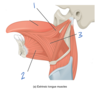

Which muscle is labeled by #2?

What is its function?

Genioglossus

-

Protrude the tonuge

- The only muscle that protrudes the tongue!

- Deviate the tongue to the opposite side

- Depress the tongue

Which structure is labeled by #3?

Geniohyoid

Which structure is labeled by #3?

Styloglossus muscle

Which muscle is labeled by #3?

What is its function?

Hyoglossus

Retract the tongue